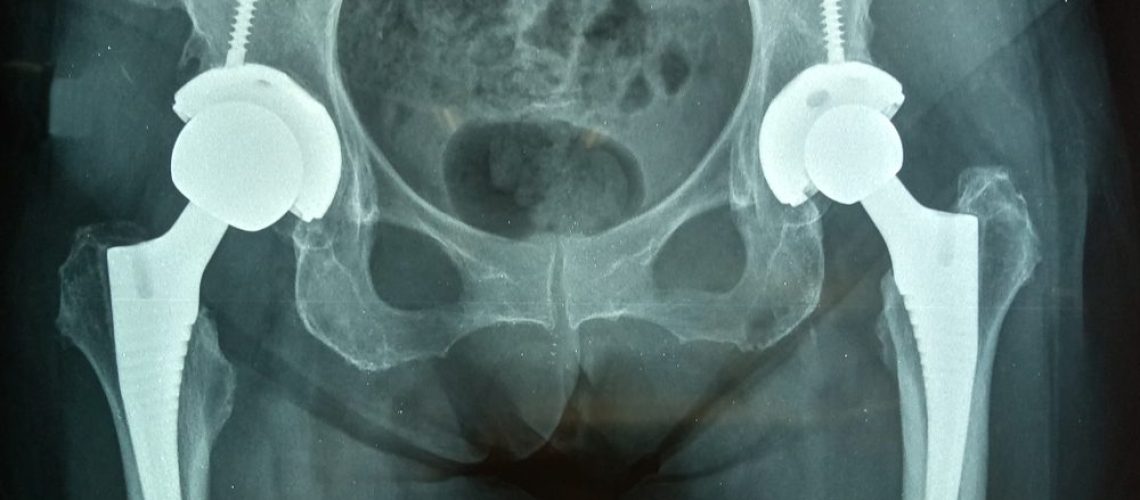

No corpo humano, temos a região da pelve, que é formada por três grandes ossos, dois ossos inominados e o osso sacro. Nos ossos inominados está o acetábulo, que possui o formato de um “y” invertido e é a superfície articular da bacia. A cartilagem acetabular é um tipo de tecido nobre que não se regenera e tem como função o suporte do peso corpóreo e a movimentação.

Quando ocorrem essas fraturas, há um impacto da cabeça femoral no acetábulo. Essas fraturas variam de acordo com o sentido da força aplicada no momento do trauma e a posição em que o quadril estava quando houve a aplicação da força. Dependendo dessas variações, a fratura acetabular terá uma característica diferente.